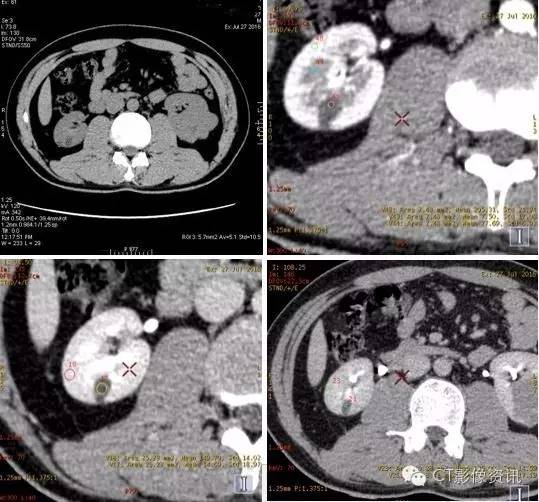

左肾病变位于左肾下极外后侧,与左肾髓质分界不清,向肾外生长并分叶。增强扫描左肾病变强化明显,皮质期病变强化程度低于左肾皮质,与左肾髓质相近,实质期及延迟期强化程度均显著低于左肾实质。

右肾病变位于右肾下极内后方,与肾实质分界清晰。增强扫描右肾病灶轻微强化,强化程度均低于右肾实质。

表一:双肾病灶及肾实质各期平扫及增强各期CT值测量结果

CT值单位:Hu 增强能谱扫描各期碘基物质图观察